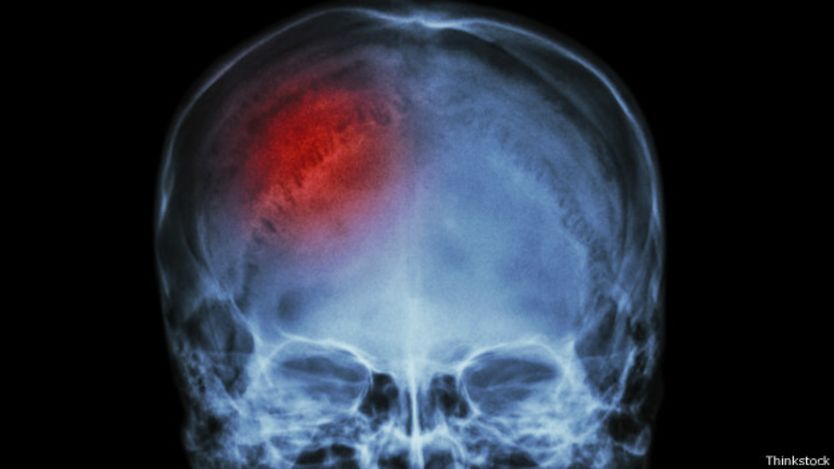

Aunque la disección de la arteria vertebral es rara, hay dos tipos de lesiones cerebrales comunes conocidas como "focales" y "difusas".

Las lesiones focales, o localizadas, tienden a ser causadas por una caída o una agresión física. Son el resultado de un daño hecho a una región del cerebro que producen un coágulo o hematoma.

Éste ocupa espacio y aumenta la presión intracraneal, cortando el oxígeno y produciendo la muerte de las células cerebrales. La manera de tratarlo es removiendo el coágulo.

Sin embargo, el daño podría no estar limitado al sitio del impacto –que se denomina "lesión de golpe".

El cerebro flota dentro del cráneo y puede chocarse contra la pared opuesta al sitio del impacto, lo que se conoce como "lesión de contragolpe".